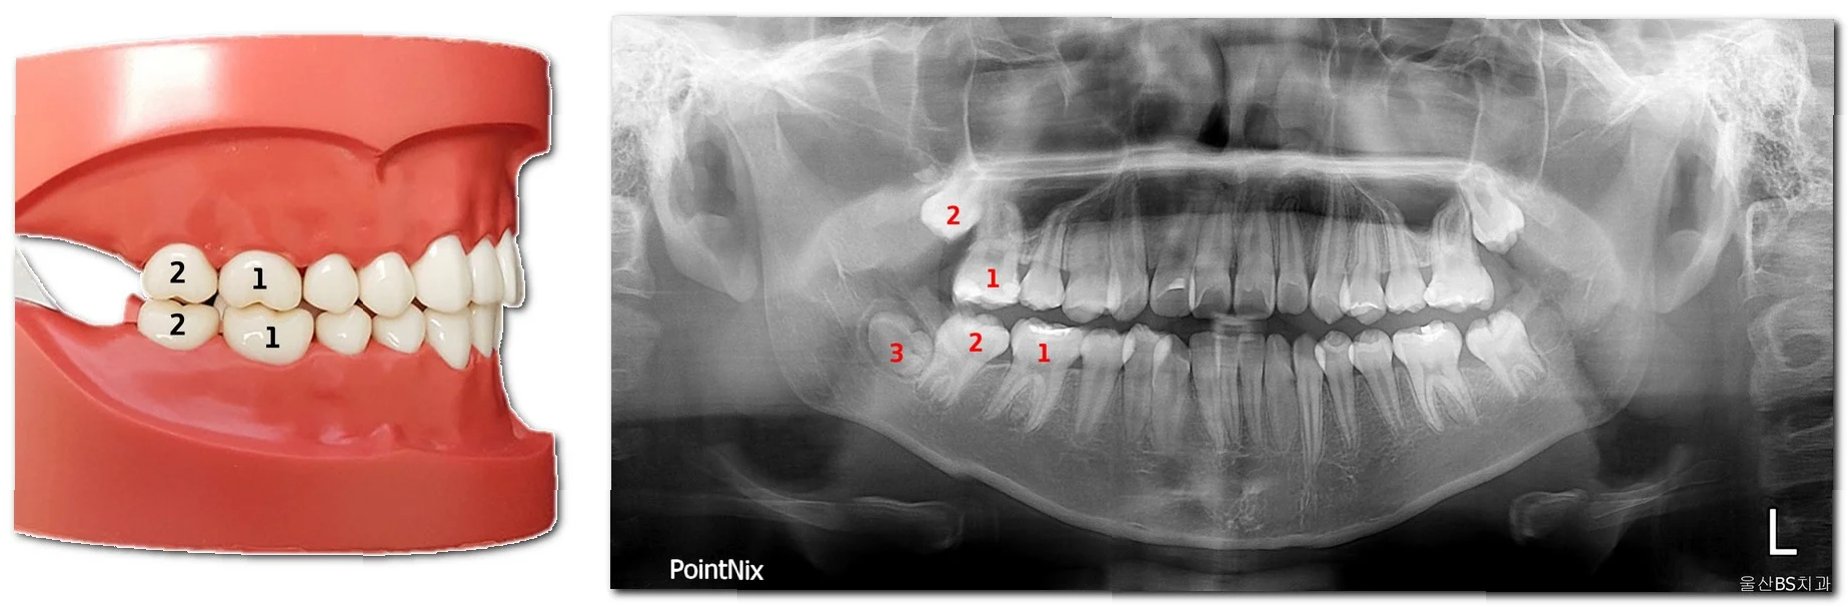

치아 맹출 지연과 이소 맹출의 치료 방법은 원인과 증상에 따라 다릅니다. 맹출 지연의 경우, 단순한 맹출 지연이라면 경과를 관찰하며 기다릴 수 있습니다. 하지만, 다른 문제가 동반된다면, 엑스레이 촬영을 통해 치아의 발육 상태를 확인하고, 맹출을 방해하는 요인(과잉치, 낭종 등)을 제거하는 치료를 진행할 수 있습니다. 이소 맹출의 경우, 치아의 위치를 바로잡기 위해 교정 치료가 필요할 수 있습니다. 덧니의 경우, 공간이 부족하다면 발치를 통해 공간을 확보하고 교정 치료를 진행할 수 있으며, 매복치의 경우, 맹출 유도술을 통해 치아를 제 위치로 나오게 할 수 있습니다. 치료 시기는 치아의 성장 상태와 환자의 상황에 따라 달라지므로, 치과 전문의와 충분히 상담하여 적절한 치료 계획을 세우는 것이 중요합니다.